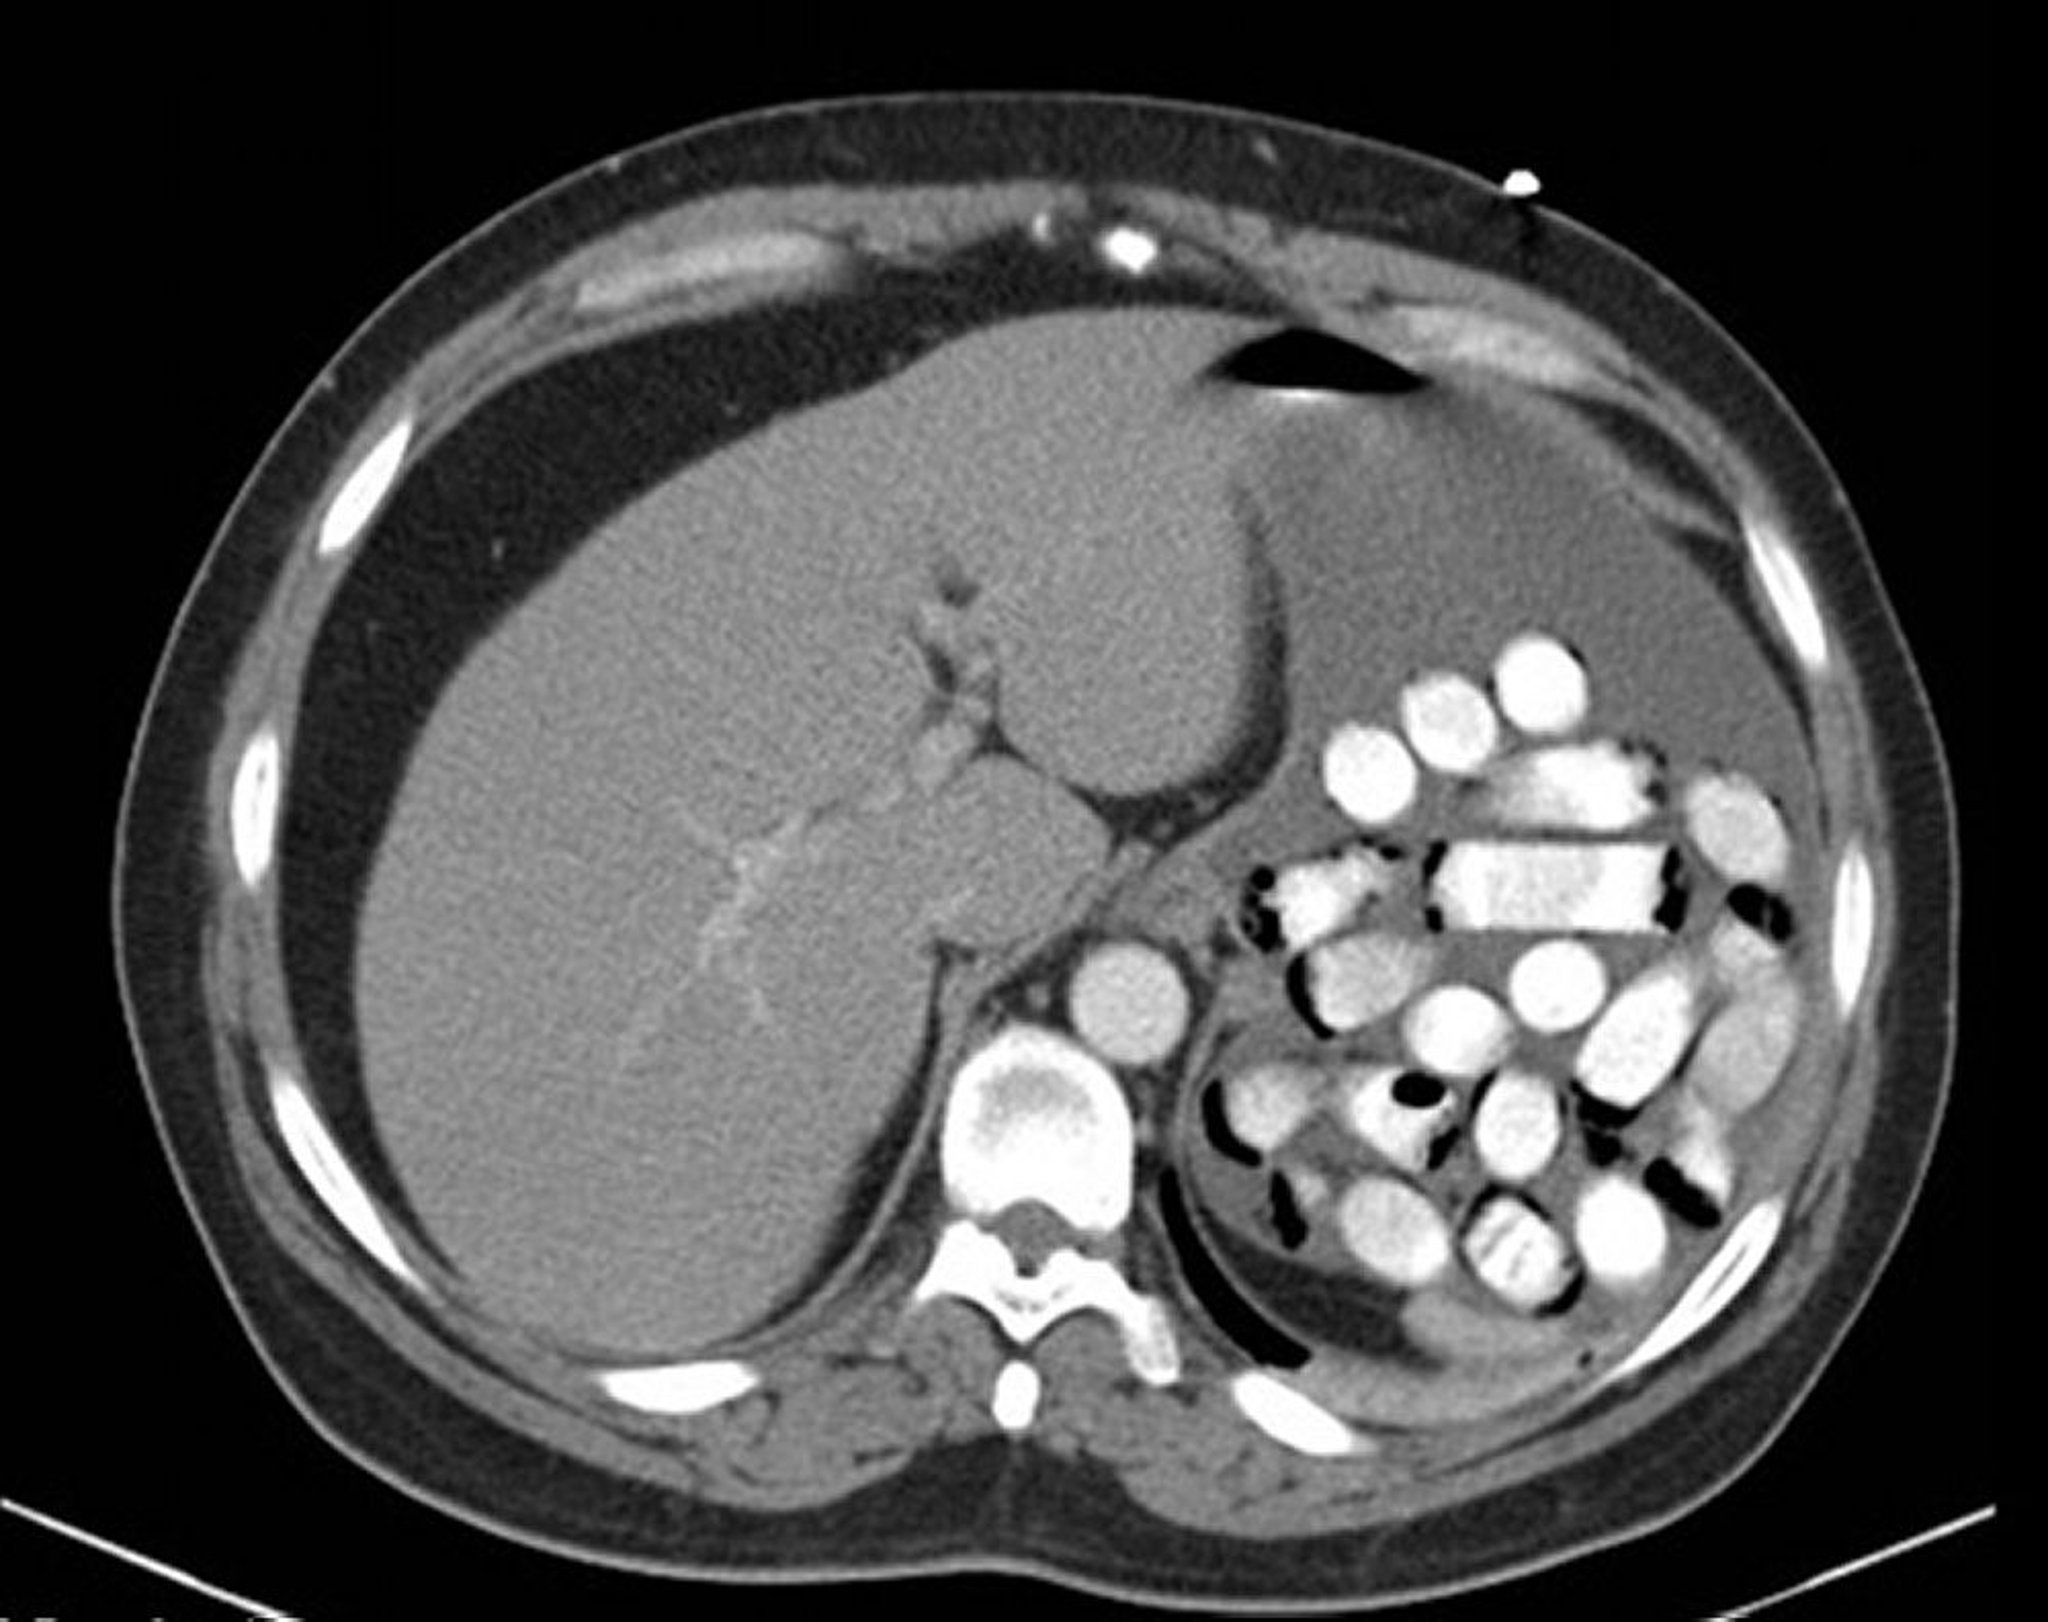

胃内異物(CT)

この画像には,胃の中にある薬物の包みが写っている。

Image provided by Alan Gingold, DO.